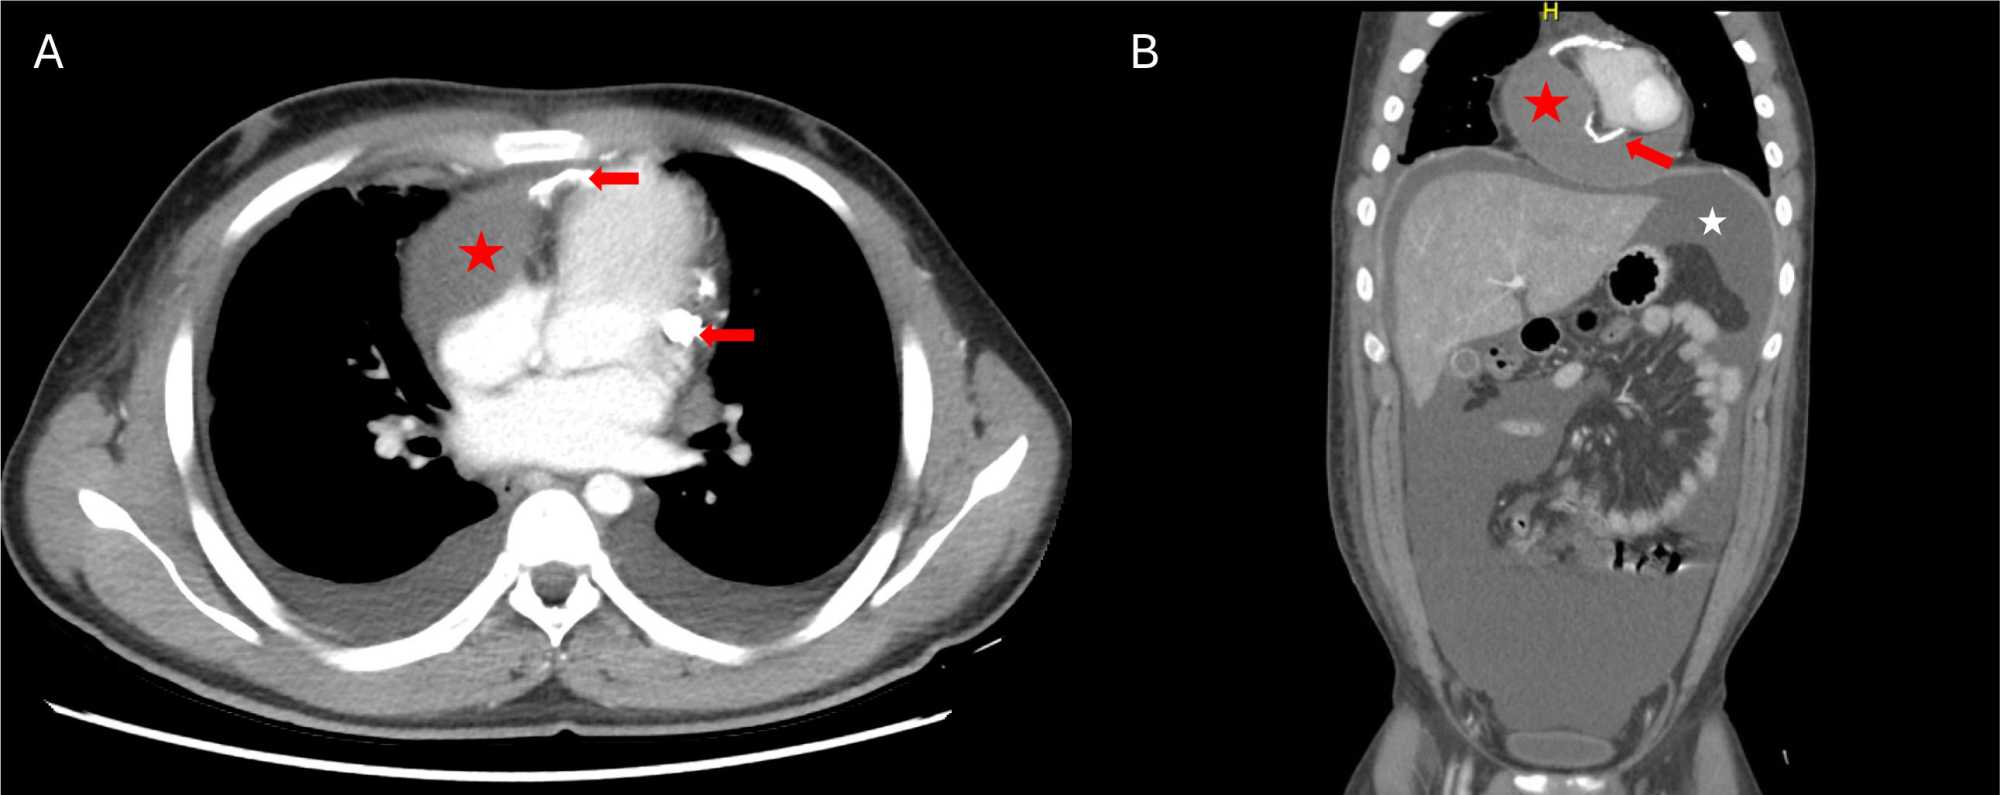

A 19-year male of Indian descent with no past medical history, presented to our emergency department with 2 weeks history of fever and abdominal pain. He also noticed increasing abdominal distention over 1 month. He did not experience any symptoms of chest pain, exertional dyspnoea or orthopnoea. Upon arrival at the emergency, he was hemodynamically stable with blood pressure of 100/74 mmHg, heart rate 87 bpm, regular, and oxygen saturation 98% on room air. His physical examination was significant for pitting pedal edema, tense abdominal ascites, and reduced air entry on auscultation bilaterally. His initial blood workup showed Hemoglobin of 15.7 g/dL, platelets of 304 × 10^3/uL, no leucocytosis and normal differential count. Inflammatory markers were elevated with C-reactive protein of 49 mg/dL and procalcitonin of 0.28 mg/dL. He had normal renal functions and mild hepatic congestion with alanine aminotransferase (ALT) of 89 U/l, aspartate transaminase (AST) 83 U/L and total bilirubin of 2.19 mg/dL with normal serum proteins. His NT-proBNP was 1898 pg/mL and cardiac enzymes were normal. Electrocardiogram was consistent with normal sinus rhythm with normal axis, intervals, and R wave progression. His chest X-ray showed a normal cardiothoracic ratio and right-sided pleural effusion. Differential diagnoses were polyserositis, constrictive pericarditis, or primary liver disease-portal hypertension. Further work-up included a chest and abdominal CT scan. It showed significant abdomino-pelvic ascites and right basal pleural effusion with right lower lobe atelectasis. All abdominal organs appeared normal. An unusual loculated extracardiac collection was noticed on the right side of the heart compressing the right atrium and right ventricle with pericardial wall calcification suggesting chronic pericarditis. Pericardial effusion was not significant. Mediastinal and retroperitoneal lymphadenopathy was not seen (Figure 1).

Figure 1. Panel (A) Chest CT scan with contrast (axial view) shows a loculated extracardiac cyst compressing the right side of heart (Red star), with heavy calcification of the pericardium (Red arrows). Panel (B) Abdomen CT scan with contrast (coronal view) with lower chest cut shows extracardiac cyst (Red star) with cyst wall calcification (Red arrow) and significant abdominopelvic ascites (white star).